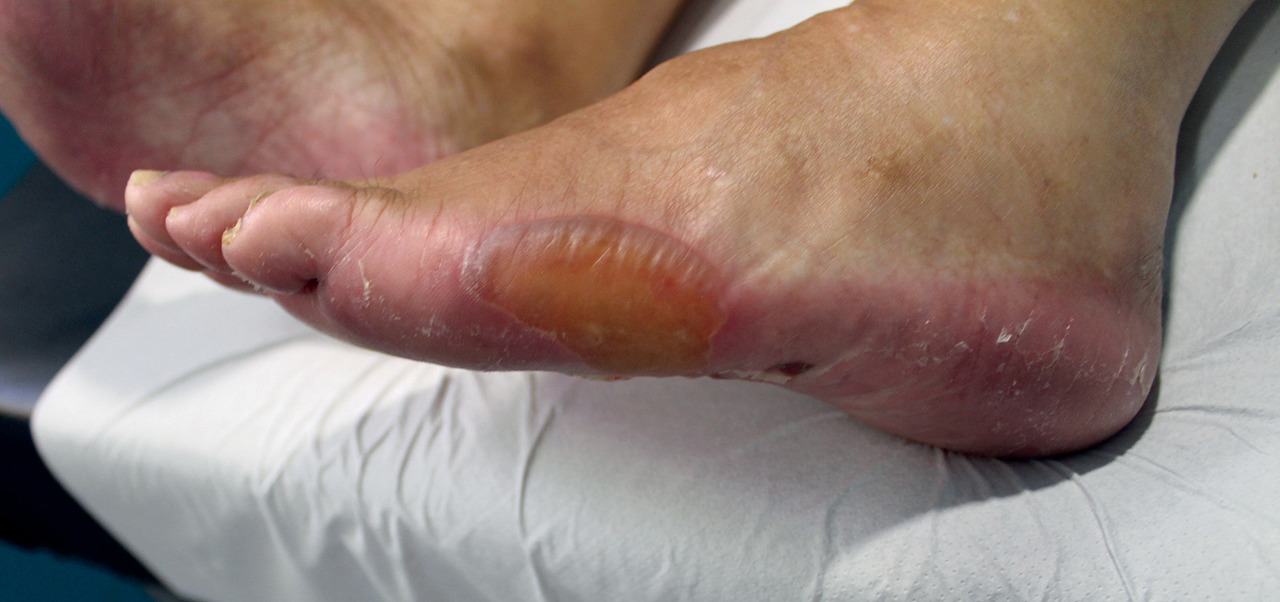

Une patiente de 84 ans consulte pour des lésions érythémato-squameuses bulleuses apparues sur les plantes des pieds. L’examen montre également un érythème des mains. En raison d’une néoplasie colique découverte il y a 3 mois, elle est sous capécitabine (7 cp par jour à J1, J14, J21 pour 8 cycles de chimiothérapie). Le jour de la consultation, elle débute le 3e cycle.

Après des paresthésies et des sensations de brûlure, un érythème de couleur rouge vif se forme surtout au niveau palmaire, associé parfois à un œdème pouvant toucher les articulations. Si, malgré ces effets secondaires, le traitement est poursuivi, les téguments peuvent devenir violacés. Bains de pieds et de mains à l’eau fraîche, port de semelles spéciales réfrigérées, application d’une crème hydratante peuvent soulager.